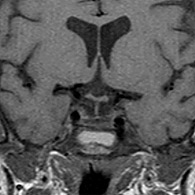

Μαγνητική τομογραφία μετά το χειρουργείο